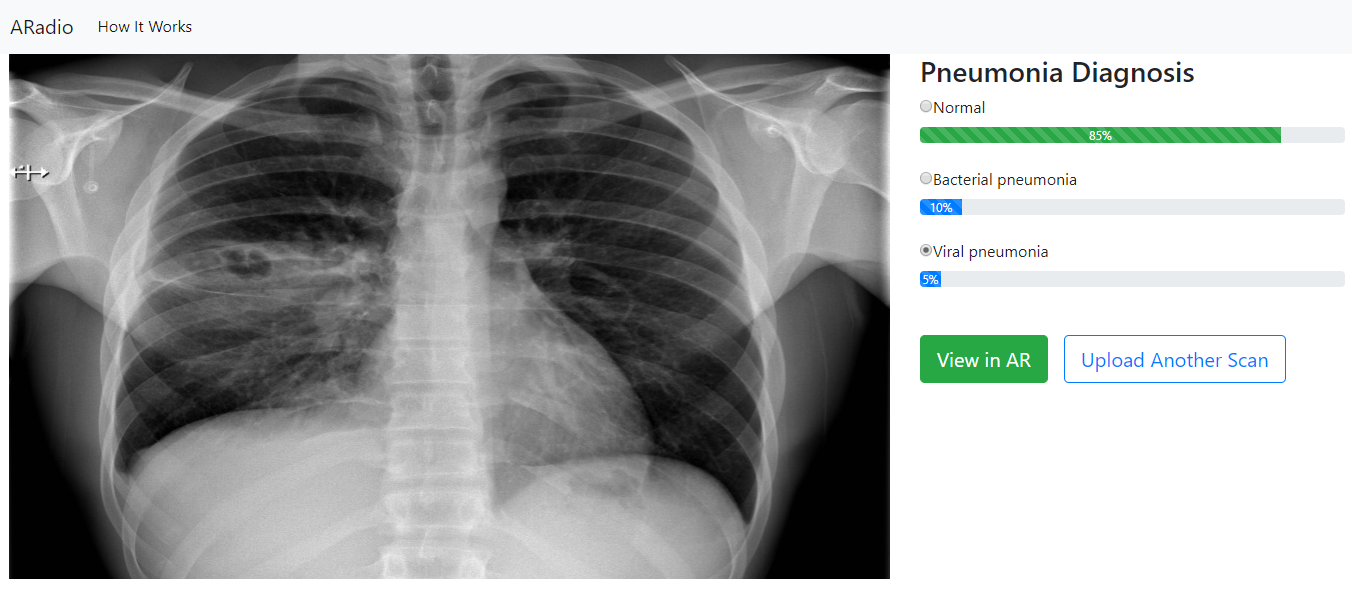

ARadio is a bespoke solution offering an image-guided solution for medical scans. A radiologist/doctor can upload a medical scan and our solution will offer recommendations on the plausible medical conditions with a confidence score. Unfortunately, 2D medical scans are limited and sometimes lead to misdiagnosis, therefore we added an augmented reality component to allow doctors to view the scan in a 3D view. And using AI, we are able to extrapolate the medical problem onto the 3D models to offer inference on the growth of the medical problems, identify optimal treatment targets, print the 3D models for surgical preparations and explore possibilities of empowering telemedicine.

Our test case was chest x-ray scans for identifying pneumonia.(Normal, Bacterial pneumonia or Viral pneumonia)